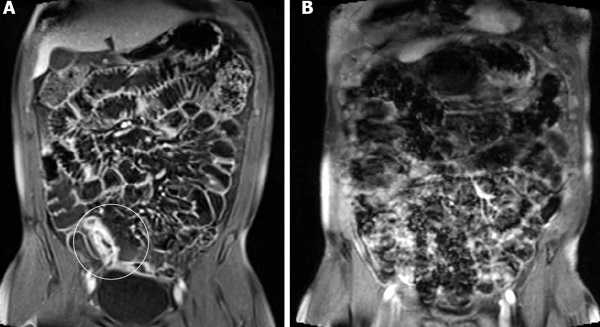

МРТ дефекография

а) Цель. При доступности, МРТ - предпочтительное исследование, поскольку позволяет визуализировать изменения внутри и вне просвета прямой кишки в течение всего времени опорожнения. В противоположность «динамической МРТ» (в положении больного лежа на спине), открытая интервенционная МРТ дефекография позволяет исследовать больного в естественном положении сидя во время естественного опорожнения кишечника.

б) Оборудование и методика:

• Требует очень дорогостоящей инфраструктуры и оборудования: сверхпроводниковая система МРТ при которой больной может сидеть.

Введение в прямую кишку МРТ контрастной пасты (гадолиний 2,5 ммоль/л): 300 мл синтетического «стула» (пюре из картофельного крахмала), смешанного с 1,5 мл гадопентата димеглюмина (377 мг/мл). Пациент садится на кресло, «прозрачное» для МРТ. Последовательность МРТ снимков: покой, удержание, натуживание, опорожнение (статические снимки или, предпочтительнее, видеодефекография).

г) Интерпретация:

• Существенные патологические изменения: качественные изменения в динамике, включая оценку состояния органов таза и брюшной полости, эффективность эвакуации, опущение тазового дна (ниже лобково-копчиковой линии), пролапс прямой кишки и органов таза, энтероцеле, расслабление лобково-прямокишечной мышцы или парадоксальное сокращение, ректоцеле, инвагинация, неполная эвакуация.